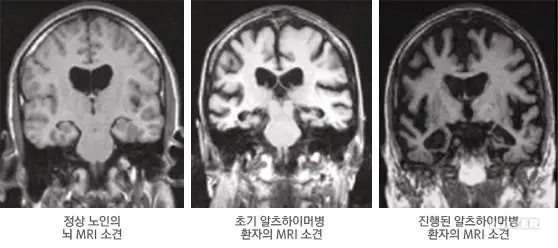

실제로, 정상인의 뇌와 치매 환자의 뇌를 찍은 MRI 영상을 비교해보면 많은 차이가 있다는 것을 알 수 있습니다. 가장 눈에 띄는 것은 해마가 있는 측두엽이 손상되어 있다는 점인데요, 그 외에도 전반적인 뇌의 모든 영역에 걸쳐서 뇌가 위축되어 있는 것을 관찰할 수 있습니다.

알츠하이머병의 MRI 영상 / 이미지출처 : 서울대학교병원 의학정보